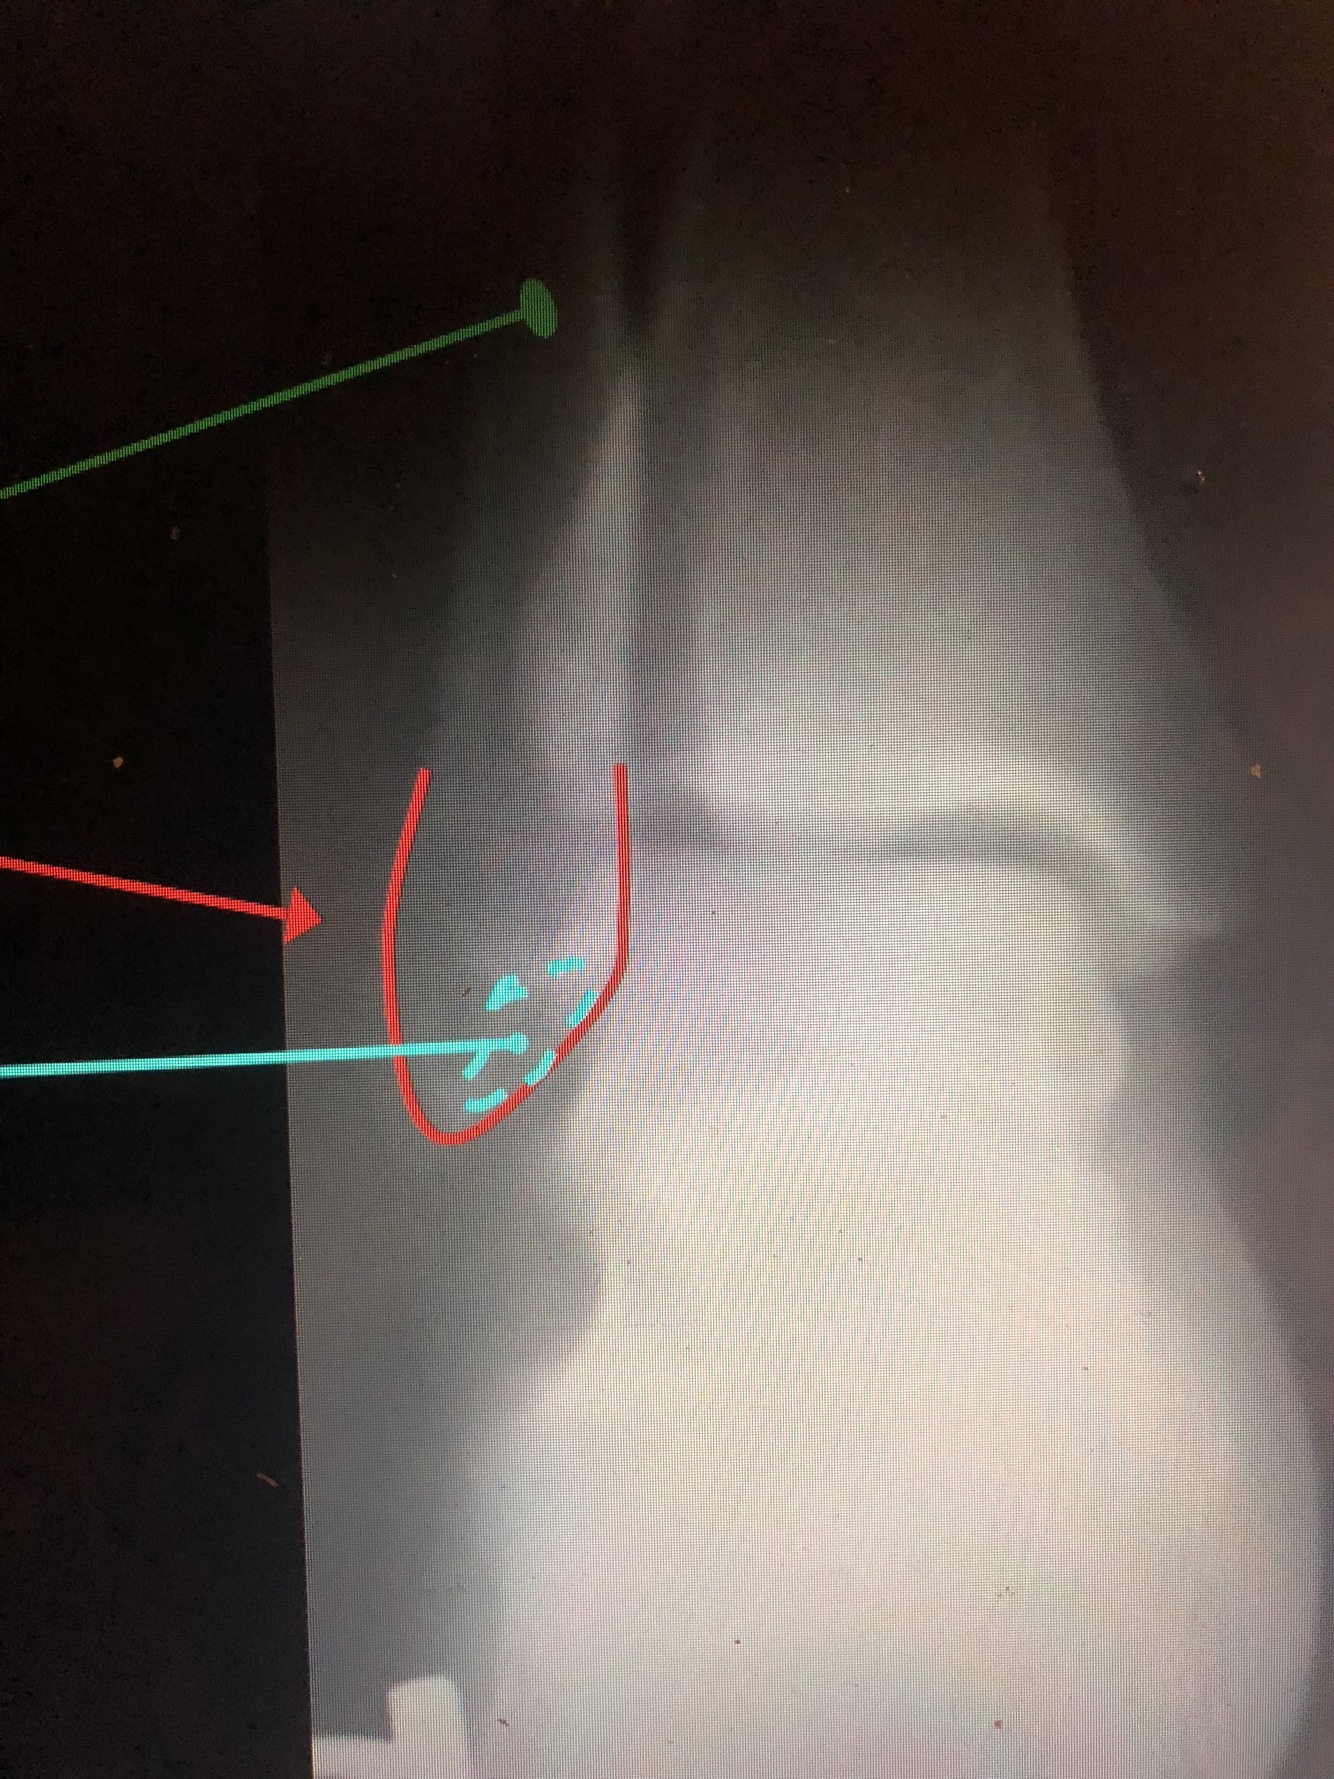

What is the light blue dotted line?

Malleolar Fossa